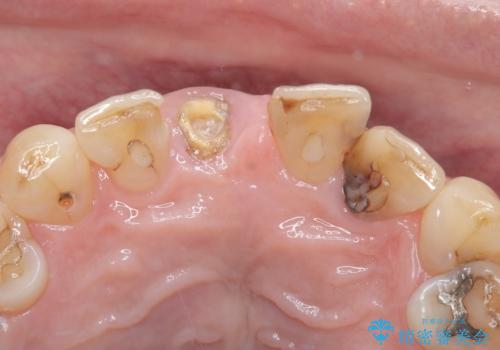

- 右上の前歯(1番)が折れたことを主訴に来院されました。診察とレントゲン検査の結果、歯冠の大部分が失われ、歯根の先には根尖病変(膿の袋)も認められました。残存歯質がほとんどなく、歯を保存することが困難と判断し、抜歯が必要と診断しました。

治療は、まず感染の原因となっていた前歯を慎重に抜歯し、抜歯と同時にインプラントを埋入しました。審美性を重視する部位であるため、骨や歯ぐきのボリュームを維持するための補填処置も併用しています。術後は仮歯を装着し、見た目を保ちながらインプラントと骨がしっかりと結合するのを待ちました。